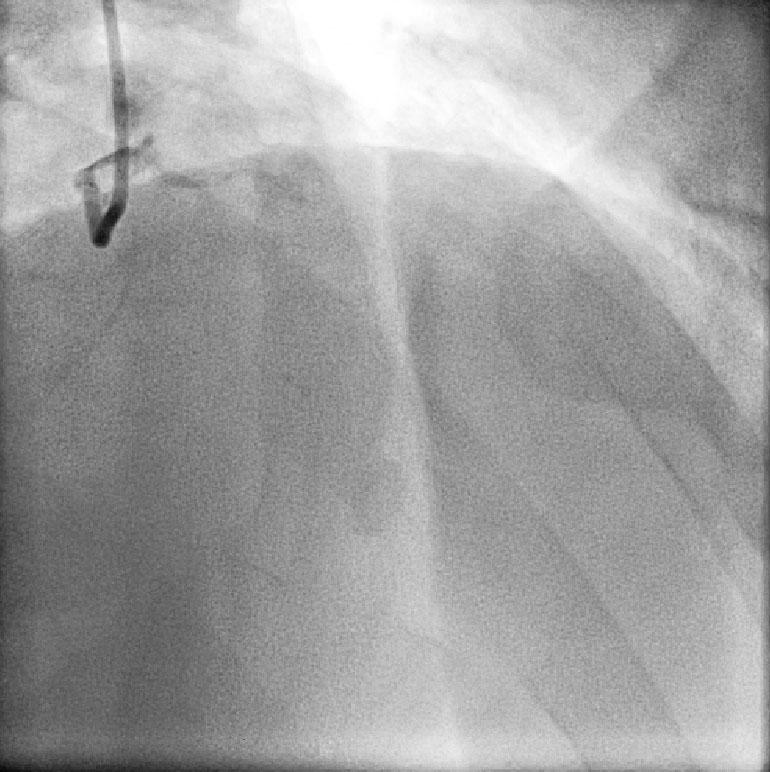

CABG in Kawasakis with Coronary Aneurysms

Angiogram prior to Primary PTCA